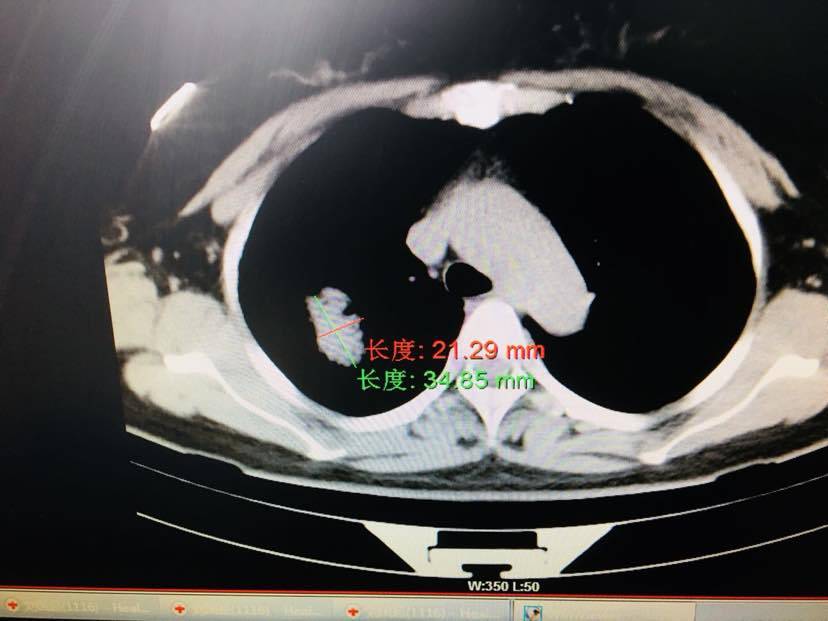

妈妈49岁右上叶肺腺癌伴胸膜转移 没有脑转和骨转 7月10号发现的 在本地医院做的手术术中医生说脏胸膜转移了做不了手术 于是做基因检测发现21L858R突变 吃的易瑞沙现在快吃40天了 前几天做CT显示靶向药效果很好原发灶没怎么变但是周围的淋巴结和一块小的转移灶全都缩小吸收 我在想会不会胸膜转移的也被靶向药消灭掉了 打算再吃几天靶向药或者用化疗打压一下?看看有没有机会手术 一直想给她手术因为觉得癌负荷太大靶向药耐药的会比较快 手术之后会不会延缓一下耐药时间? 还是应该老老实实的吃靶向易瑞沙9291PD1这样 请您指点